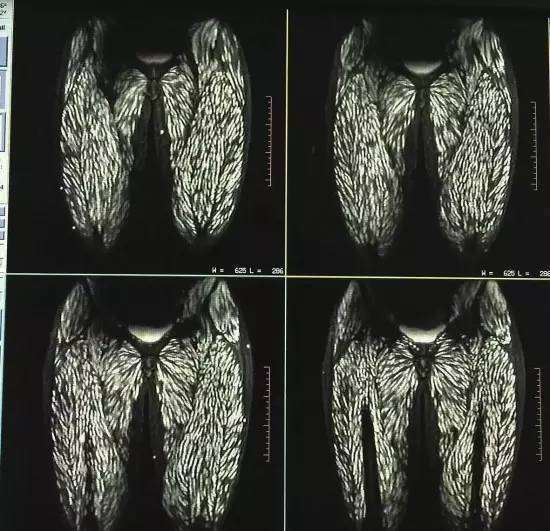

不料所有的檢查結果一出爐,馬上嚇壞了一旁看X光片的醫護人員,就連行醫多年的主治醫生都驚訝連連:簡直太不可思議了!原來從各種的各種影像檢查資料來看,眼球後方、大腿、腹壁、背部肌肉多個地方都長滿了寄生蟲,就連舌頭、臉部肌肉也有感染。抽血檢查後更進一步證實,婷婷的囊蟲抗體是陽性,屬於囊蟲感染。

▼畫面上布滿的白點,就是感染的寄生蟲。

由於婷婷生吃豬肉有一段歷史了,讓醫生發現到她的大腦裡有囊蟲鈣化現象,這表示裡面有囊蟲死去。而且患者眼球突出,視網膜出血,全身多處感染,會伴隨著癲癇發作,如此嚴重的狀況也是醫生第一次遇見。